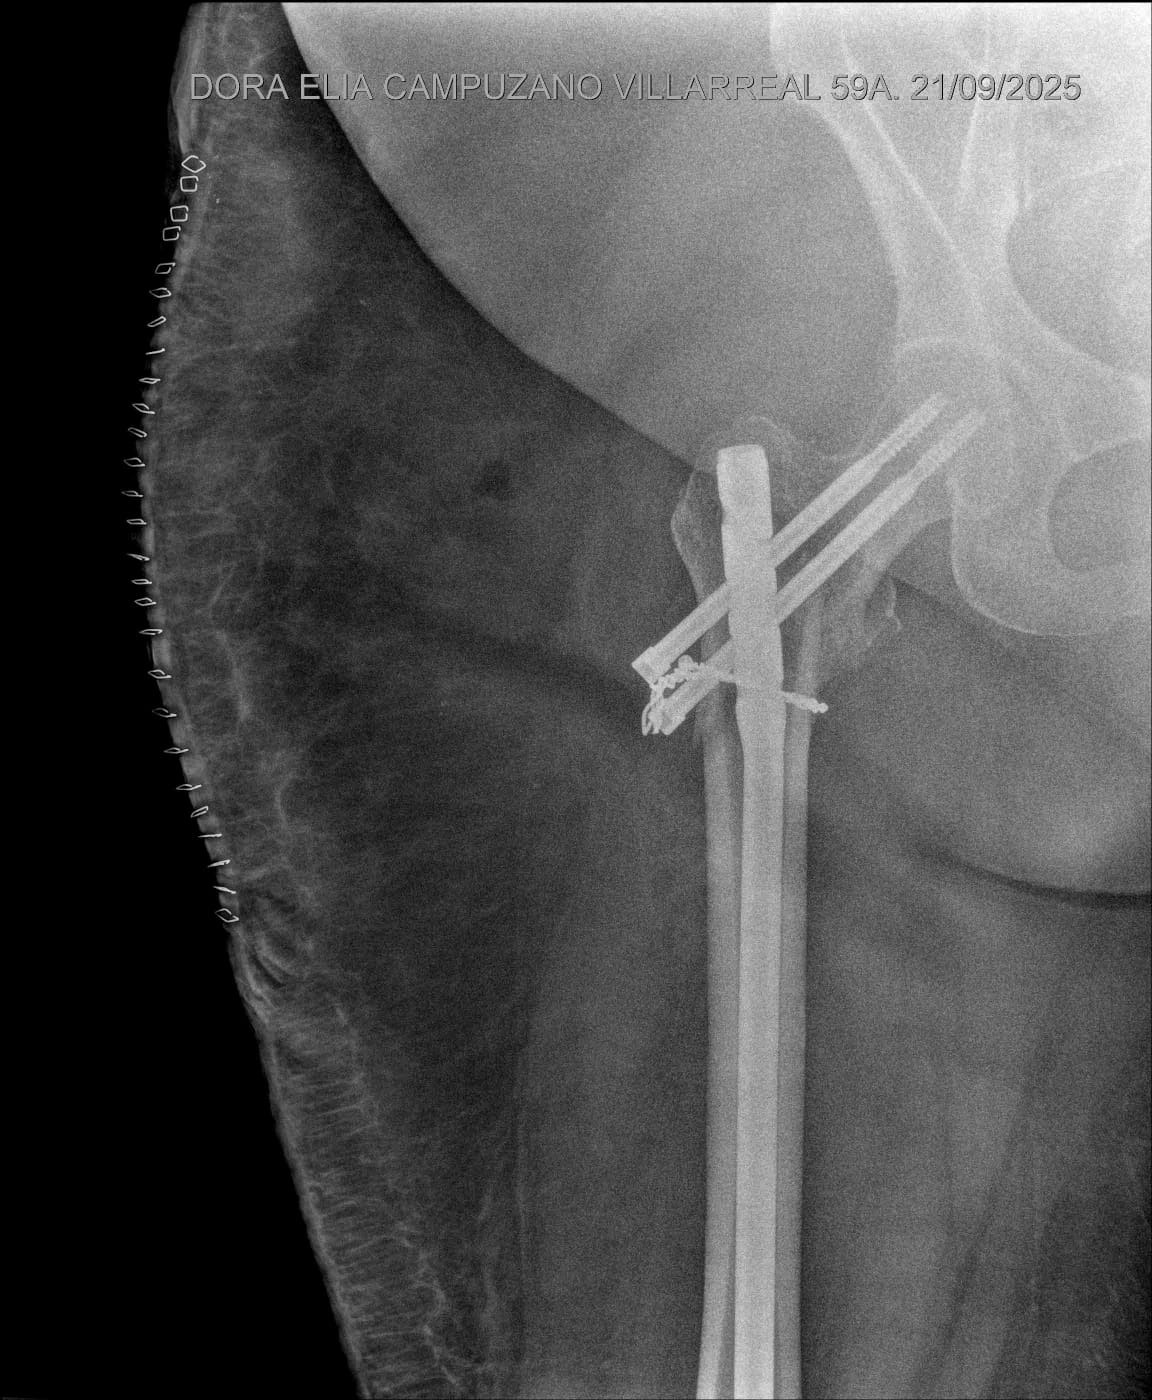

Hace poco sufrí un accidente al resbalarme en la lluvia, lo que me provocó una fractura complicada en el fémur/cadera. Debido a la inclinación de la fractura y la grasa alrededor de la pierna, los doctores no pudieron usar el procedimiento habitual, lo que elevó los costos de la cirugía.